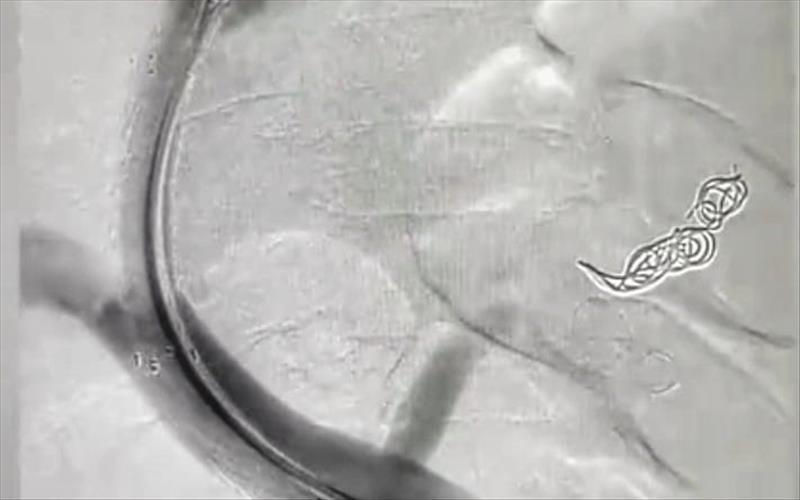

70 yaşındaki siroz hastasına TİPS işlemi uygulandı

SEAH Girişimsel Radyoloji Kliniğinde ilk defa varis kanamalarının ve karında su toplanmasının önüne